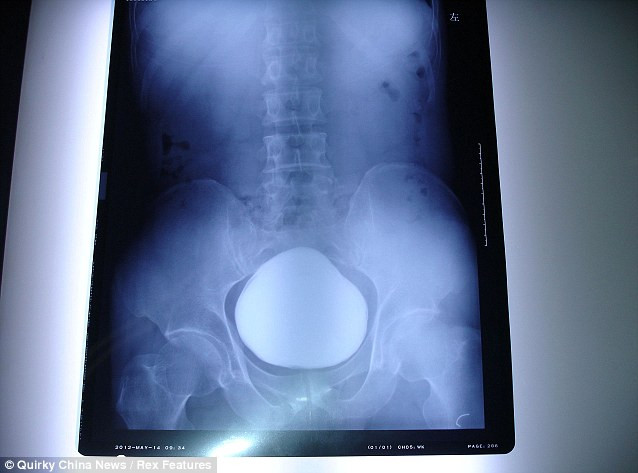

| Ảnh chụp X-quang thấy rõ cục sỏi khổng lồ. Ảnh: Chinanews. |

Bệnh nhân họ Trương, 43 tuổi, được đưa tới bệnh viện thành phố Vũ Hán để khám sau khi ông than thở rằng việc tiểu tiện ngày một đau đớn và khó khăn.

Các nhân viên y tế đã tiến hành chụp X- quang cho ông và họ đã sửng sốt khi phát hiện một vật thể khổng lồ rộng 11 cm nằm gọn trong bàng quang của bệnh nhân.